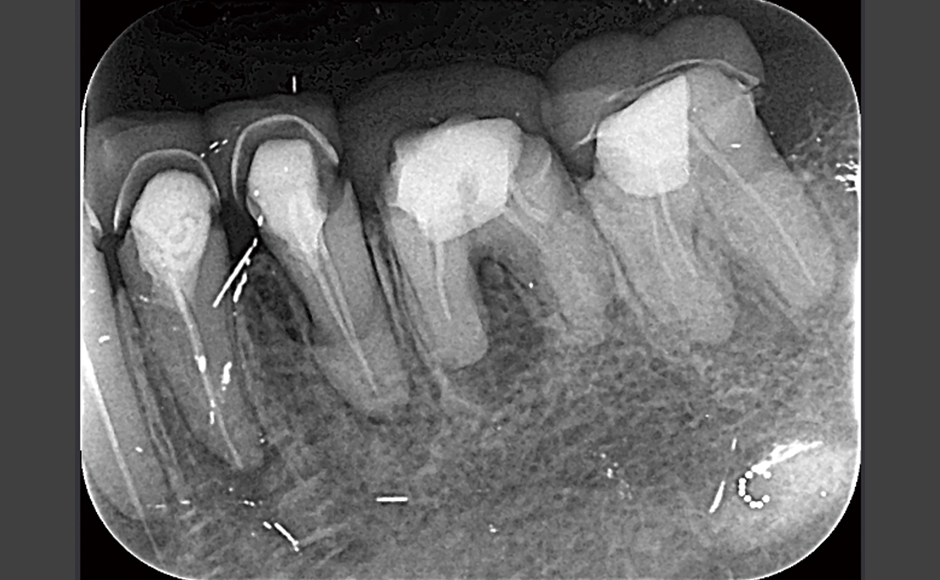

レーザーの応用による効果的な根管治療 症例1:多数歯に対してのレーザー使用 症例2:歯根嚢胞に対し外科的処置とレーザー併用